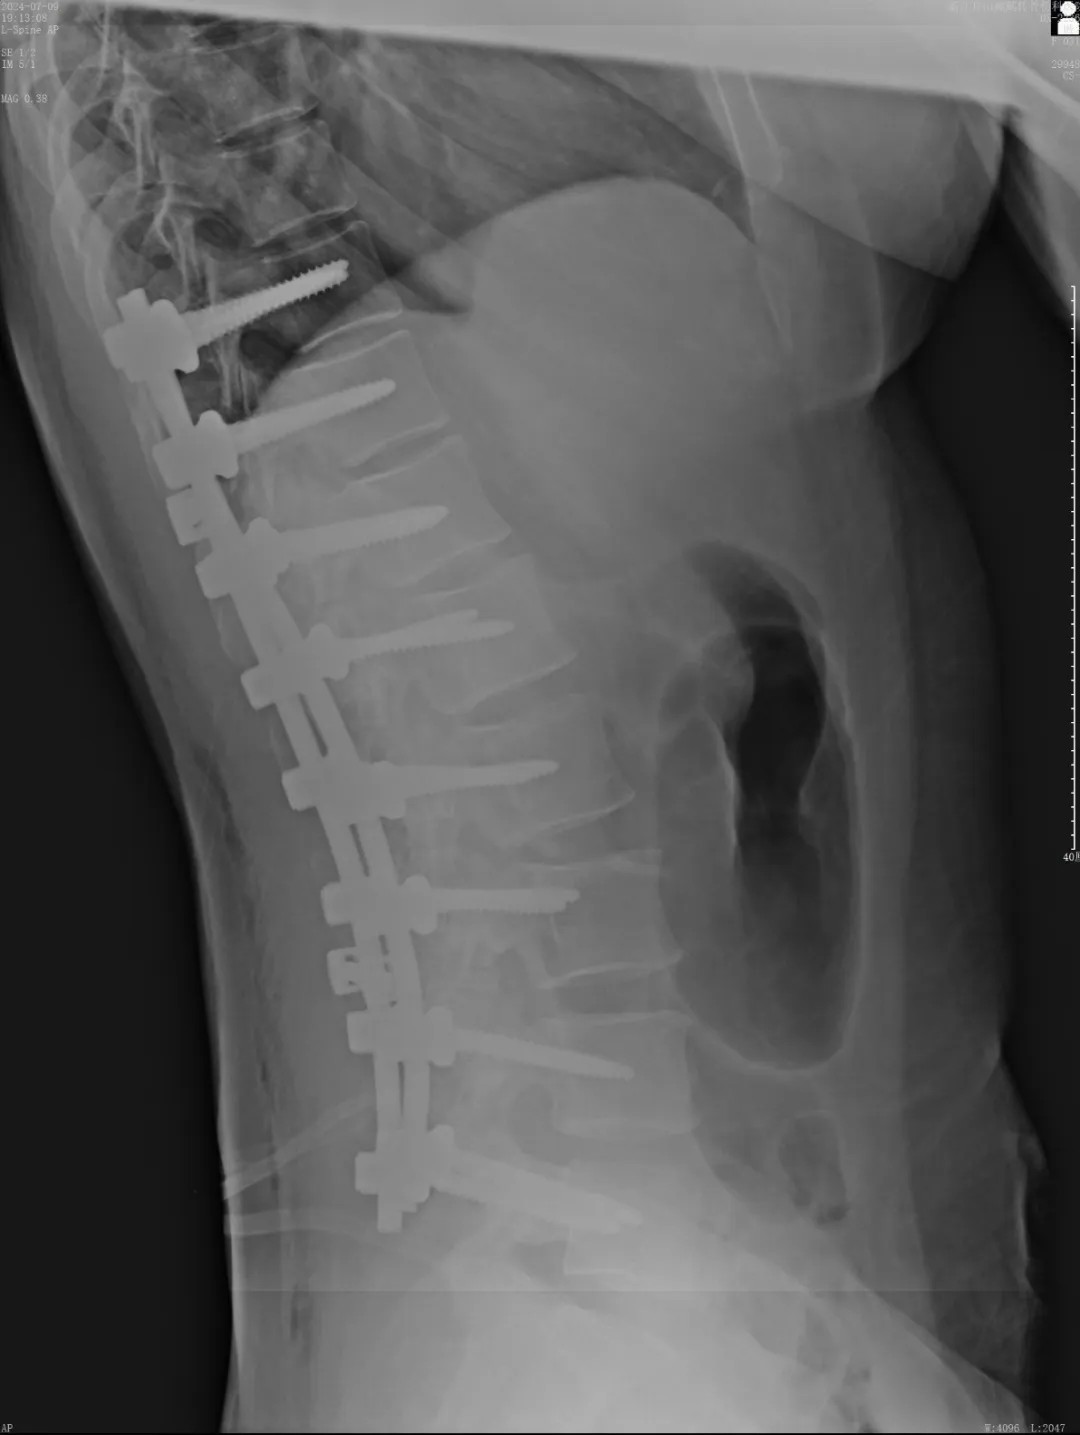

在充分的術(shù)前準(zhǔn)備后,脊柱科、微創(chuàng)治療中心專家團(tuán)隊(duì)為文女士(化名)進(jìn)行了脊柱側(cè)彎矯形、植骨融合內(nèi)固定術(shù),歷經(jīng)近4個(gè)半小時(shí)的精細(xì)操作,手術(shù)圓滿完成。術(shù)中全程使用術(shù)中電生理監(jiān)測(cè)系統(tǒng),每步都力求精準(zhǔn)細(xì)致。

近日,文女士(化名)來院復(fù)診,整體恢復(fù)良好,術(shù)前活動(dòng)不便的癥狀明顯好多了,腰背部肌肉也恢復(fù)了一些,脊柱生理曲度相比術(shù)前有所恢復(fù),側(cè)彎癥狀也明顯改善,下胸椎、腰椎向左側(cè)側(cè)凸畸形較前改善,腰背部轉(zhuǎn)側(cè)活動(dòng)不利較前改善。